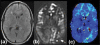

Moyamoya disease is characterized by a chronic stenoocclusive vasculopathy affecting the terminal internal carotid arteries. The clinical presentation and outcome of moyamoya disease remain varied based on angiographic studies alone, and much work has been done to study cerebral hemodynamics in this group of patients. The ability to measure cerebral blood flow (CBF) accurately continues to improve with time, and with it a better understanding of the pathophysiological mechanisms in patients with moyamoya disease. The main imaging techniques used to evaluate cerebral hemodynamics include PET, SPECT, xenon-enhanced CT, dynamic perfusion CT, MR imaging with dynamic susceptibility contrast and with arterial spin labeling, and Doppler ultrasonography. More invasive techniques include intraoperative ultrasonography. The authors review the current knowledge of CBF in this group of patients and the role each main quantitative method has played in evaluating them, both in the disease state and after surgical intervention.